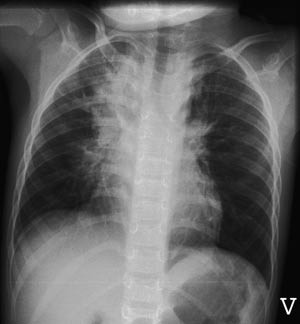

Pasient 2. En sju år gammel jente med asthma bronchiale som ble innlagt med økende obstruktivitet etter en forkjølelse. Ved innleggelsen var oksygenmetningen 87 % og temperaturen 39,2 °C. Røntgen thorax viste uttalte bilaterale hilusnære infiltrater med atelektatisk preg og en stor atelektatisk fortetning i høyre lungetopp (fig 5). CRP var 13 mg/l. Det ble påvist humant metapneumovirus i nasopharynxaspirat. Hun testet negativt for andre luftveisvirus. På tross av hyppige inhalasjoner (adrenalin, salbutamol og budesonid) og metylprednisolon intravenøst, tilkom forverret hypoksi og økende infiltrater. Initial intravenøs penicillinbehandling ble skiftet til intravenøs erytromycin etter noen dager. Serologi for Mycoplasma pneumoniae var imidlertid negativ. Hun fikk oksygentilskudd i sju dager og var innlagt i 11 dager. Hun har ikke hatt akutt astmaforverring senere.